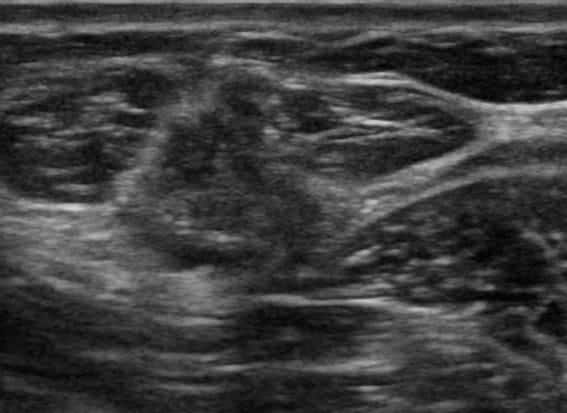

Ung thư vú

» Thông tin: Nữ giới – 41 tuổi.

» Lâm sàng: Khối tuyến vú.